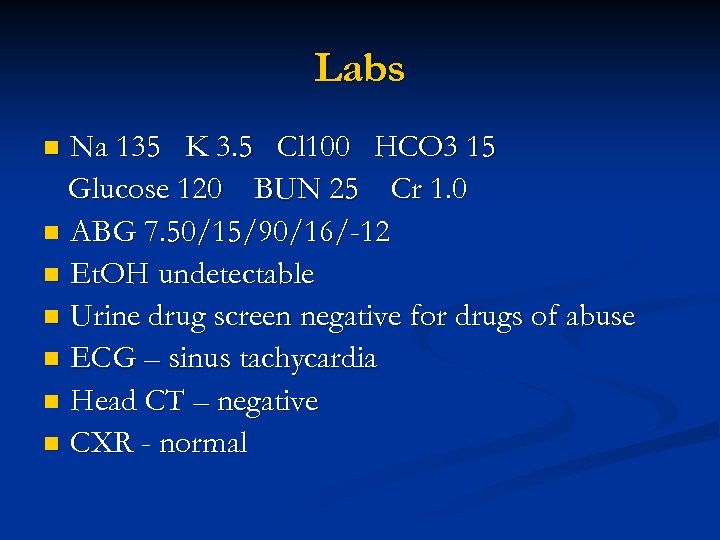

Labs Na 135 K 3. 5 Cl 100 HCO 3 15 Glucose 120 BUN 25 Cr 1. 0 n ABG 7. 50/15/90/16/-12 n Et. OH undetectable n Urine drug screen negative for drugs of abuse n ECG – sinus tachycardia n Head CT – negative n CXR - normal n

Labs Na 135 K 3. 5 Cl 100 HCO 3 15 Glucose 120 BUN 25 Cr 1. 0 n ABG 7. 50/15/90/16/-12 n Et. OH undetectable n Urine drug screen negative for drugs of abuse n ECG – sinus tachycardia n Head CT – negative n CXR - normal n